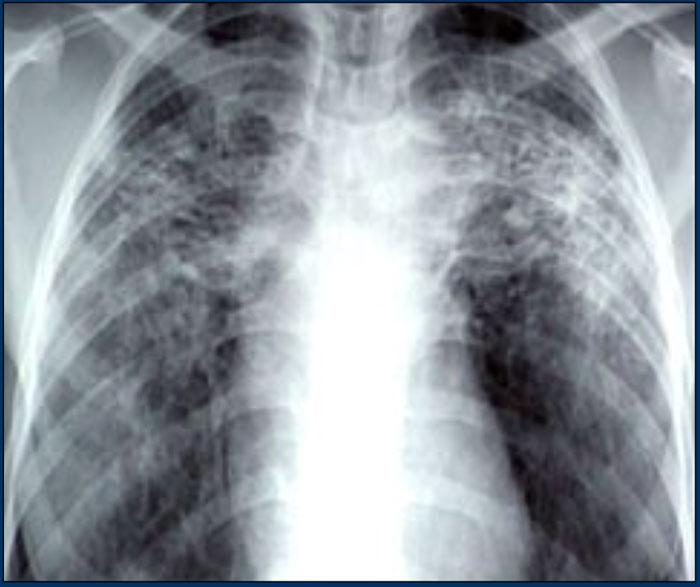

Bên trái là bệnh nhân nữ 47 tuổi với triệu chứng ho khan, khó thở nhẹ và xét nghiệm máu bình thường.

Bệnh nhân được chụp X-quang ngực và điều trị kháng sinh.

Phim kiểm tra được chụp lại do bệnh nhân không cải thiện.

Phim X-quang ngực đầu tiên cho thấy đông đặc hai bên ở thùy dưới (mũi tên), ban đầu được diễn giải là nhiễm trùng.

Sau hai tuần điều trị kháng sinh, không có cải thiện.

Chẩn đoán phân biệt lúc này bao gồm u ác tính (ung thư phế quản phế nang hoặc u lympho), viêm phổi tăng bạch cầu ái toan, viêm phổi tổ chức hóa, bệnh Wegener hoặc một thể không điển hình của sarcoidosis.

Tiếp tục với hình ảnh HRCT.

Hãy cuộn qua các hình ảnh bên trái.

Có nhiều vùng đông đặc.

Các dấu hiệu kèm theo bao gồm hạch to rốn phổi và trung thất.

Chẩn đoán phân biệt trên hình ảnh CT về cơ bản giống như trên X-quang ngực.

Kết quả mô bệnh học xác nhận sarcoidosis phế nang.

Chỉ có một gợi ý duy nhất cho chẩn đoán, đó là sự hiện diện của các nốt nhỏ có thể nhận thấy ở hình 3, nhưng rất khó quan sát.

Trường hợp này minh họa rõ ràng rằng sarcoidosis thực sự là “kẻ bắt chước vĩ đại”.

Do đó, sarcoidosis cần được đưa vào danh sách chẩn đoán phân biệt của chúng ta!